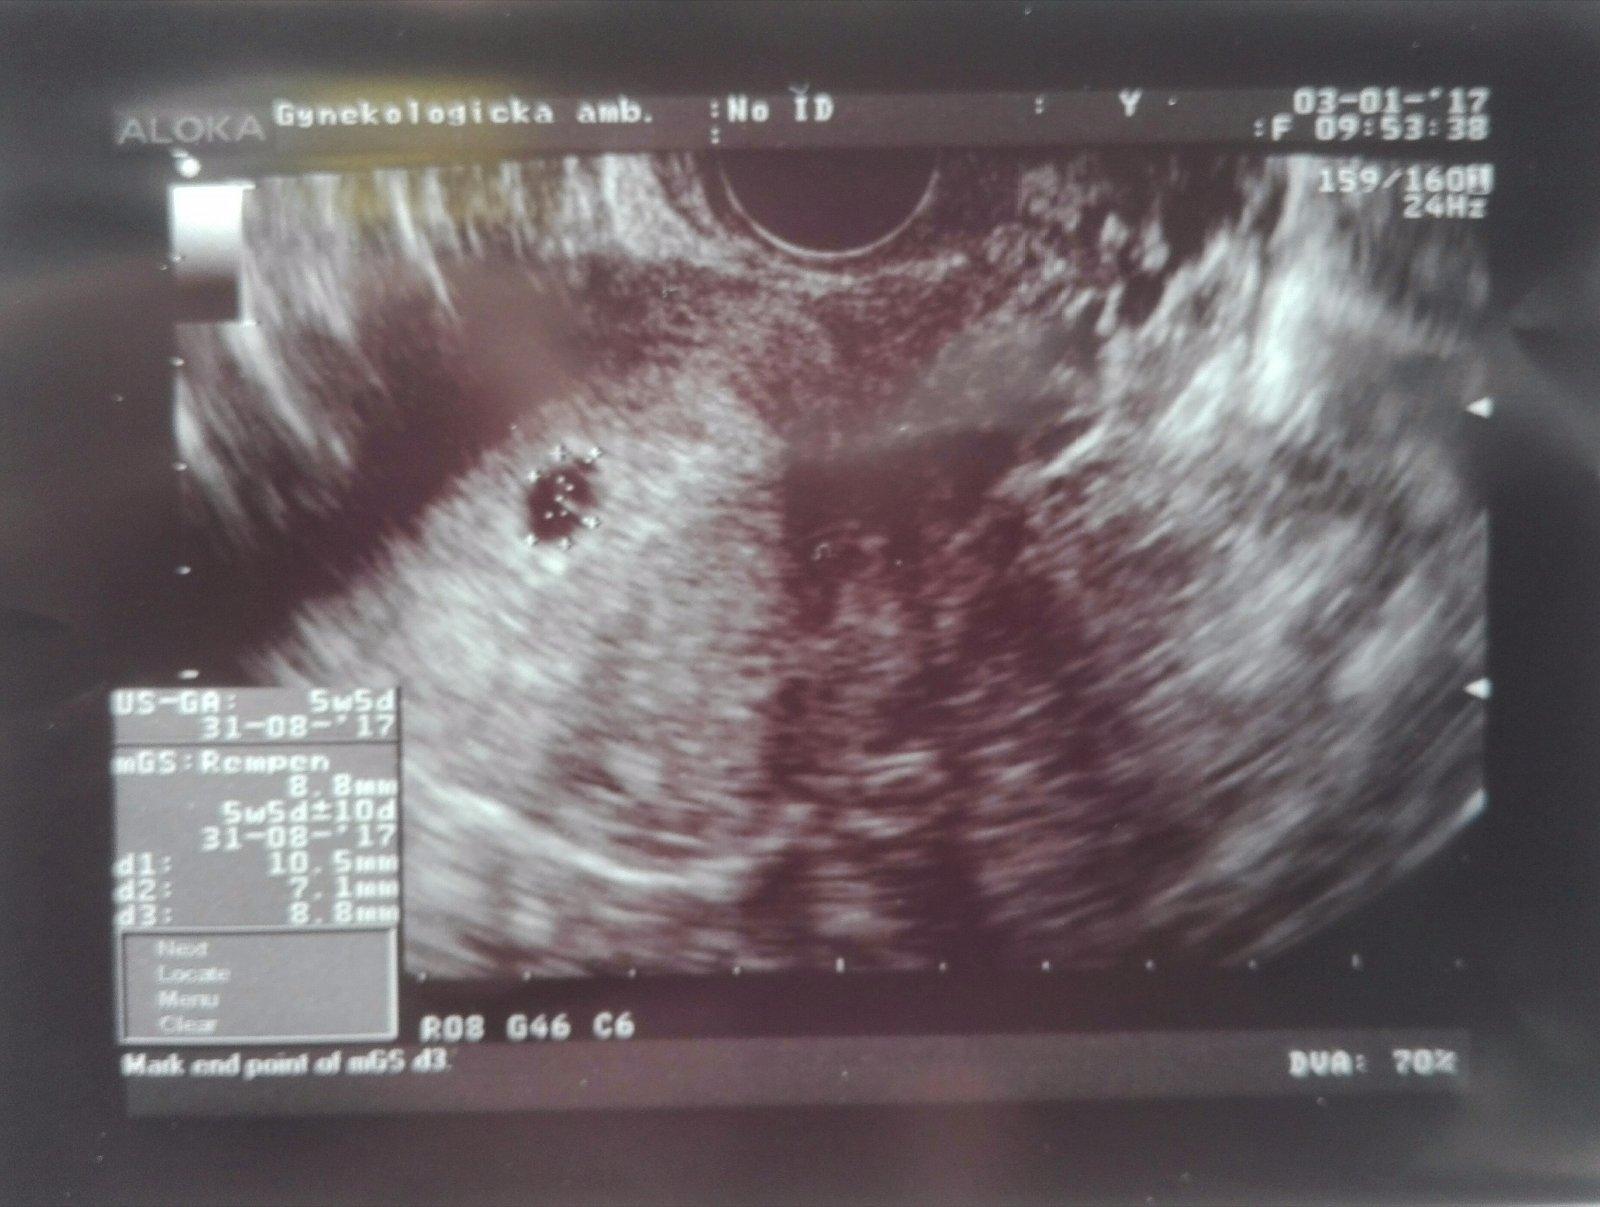

@luta13 dakujem zo ❤ testik z 2.1. a prve foto nasej fazulky.Podla PM som 3.1. bola 6tt+2,ale podla sona 5tt+5.Dr.povedal,ze taka odchylka je este vporiadku.Dalsie sono nas caka 16.1.,ci uz bude srdiecko.Drz nam prosim palce,nech vidime srdiecko krasne bit. 😉